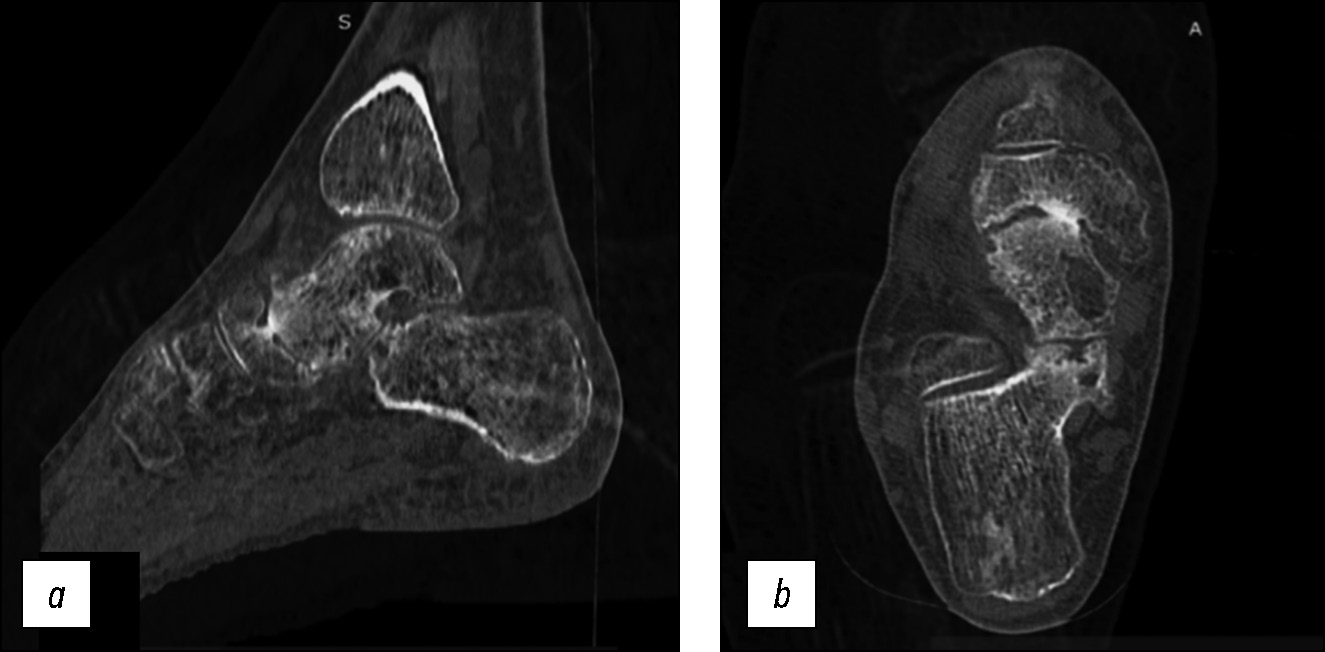

По данным рентгенографии с нагрузкой и компьютерной томографии признаков нестабильности эндопротеза головки таранной кости не отмечено (рис. 10, 11).

Рис. 11. Сагиттальный срез компьютерной томограммы правого голеностопного сустава и стопы через 24 месяца после проведённого лечения: не определяются лизис около ножки эндопротеза, признаки прогрессирования дегенеративных изменений суставной поверхности ладьевидной кости.

Fig. 11. Sagittal section of a CT scan of the right ankle joint and foot 24 months after treatment: no lysis was detected near the leg of the endoprosthesis, no signs of progression of degenerative changes in the articular surface of the scaphoid bone.